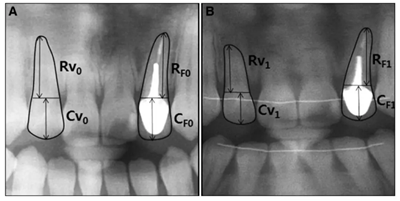

方法:研究樣本由35名年齡在25.23±4.92歲的患者組成,他們?cè)谡委熐爸辽儆?根牙根填充。在正畸治療之前和之后采集的每個(gè)患者的全景片用于測(cè)量EARR。應(yīng)用匹配對(duì)的 t檢驗(yàn)和Pearson相關(guān)分析。

結(jié)果:根充牙平均EARR值為0.22(0.14,0.35),對(duì)側(cè)活髓牙的平均EARR值為0.87(0.59,1.31),與活髓牙相比,根充牙的EARR顯著降低。 EARR受患者年齡,治療持續(xù)時(shí)間,治療類(lèi)型和根尖周病變的影響,但不受牙齒類(lèi)型和性別的影響。